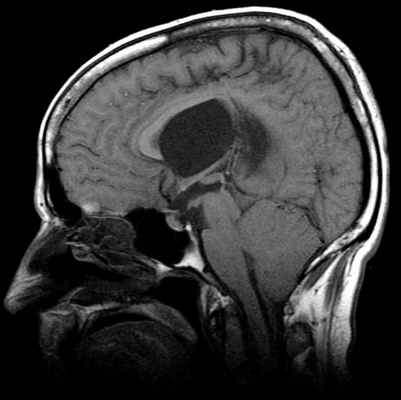

МР-картина ААК II типа – четко визуализируется каудальное смещении нижних отделов червя мозжечка,

продолговатого мозга, а также гидроцефалия